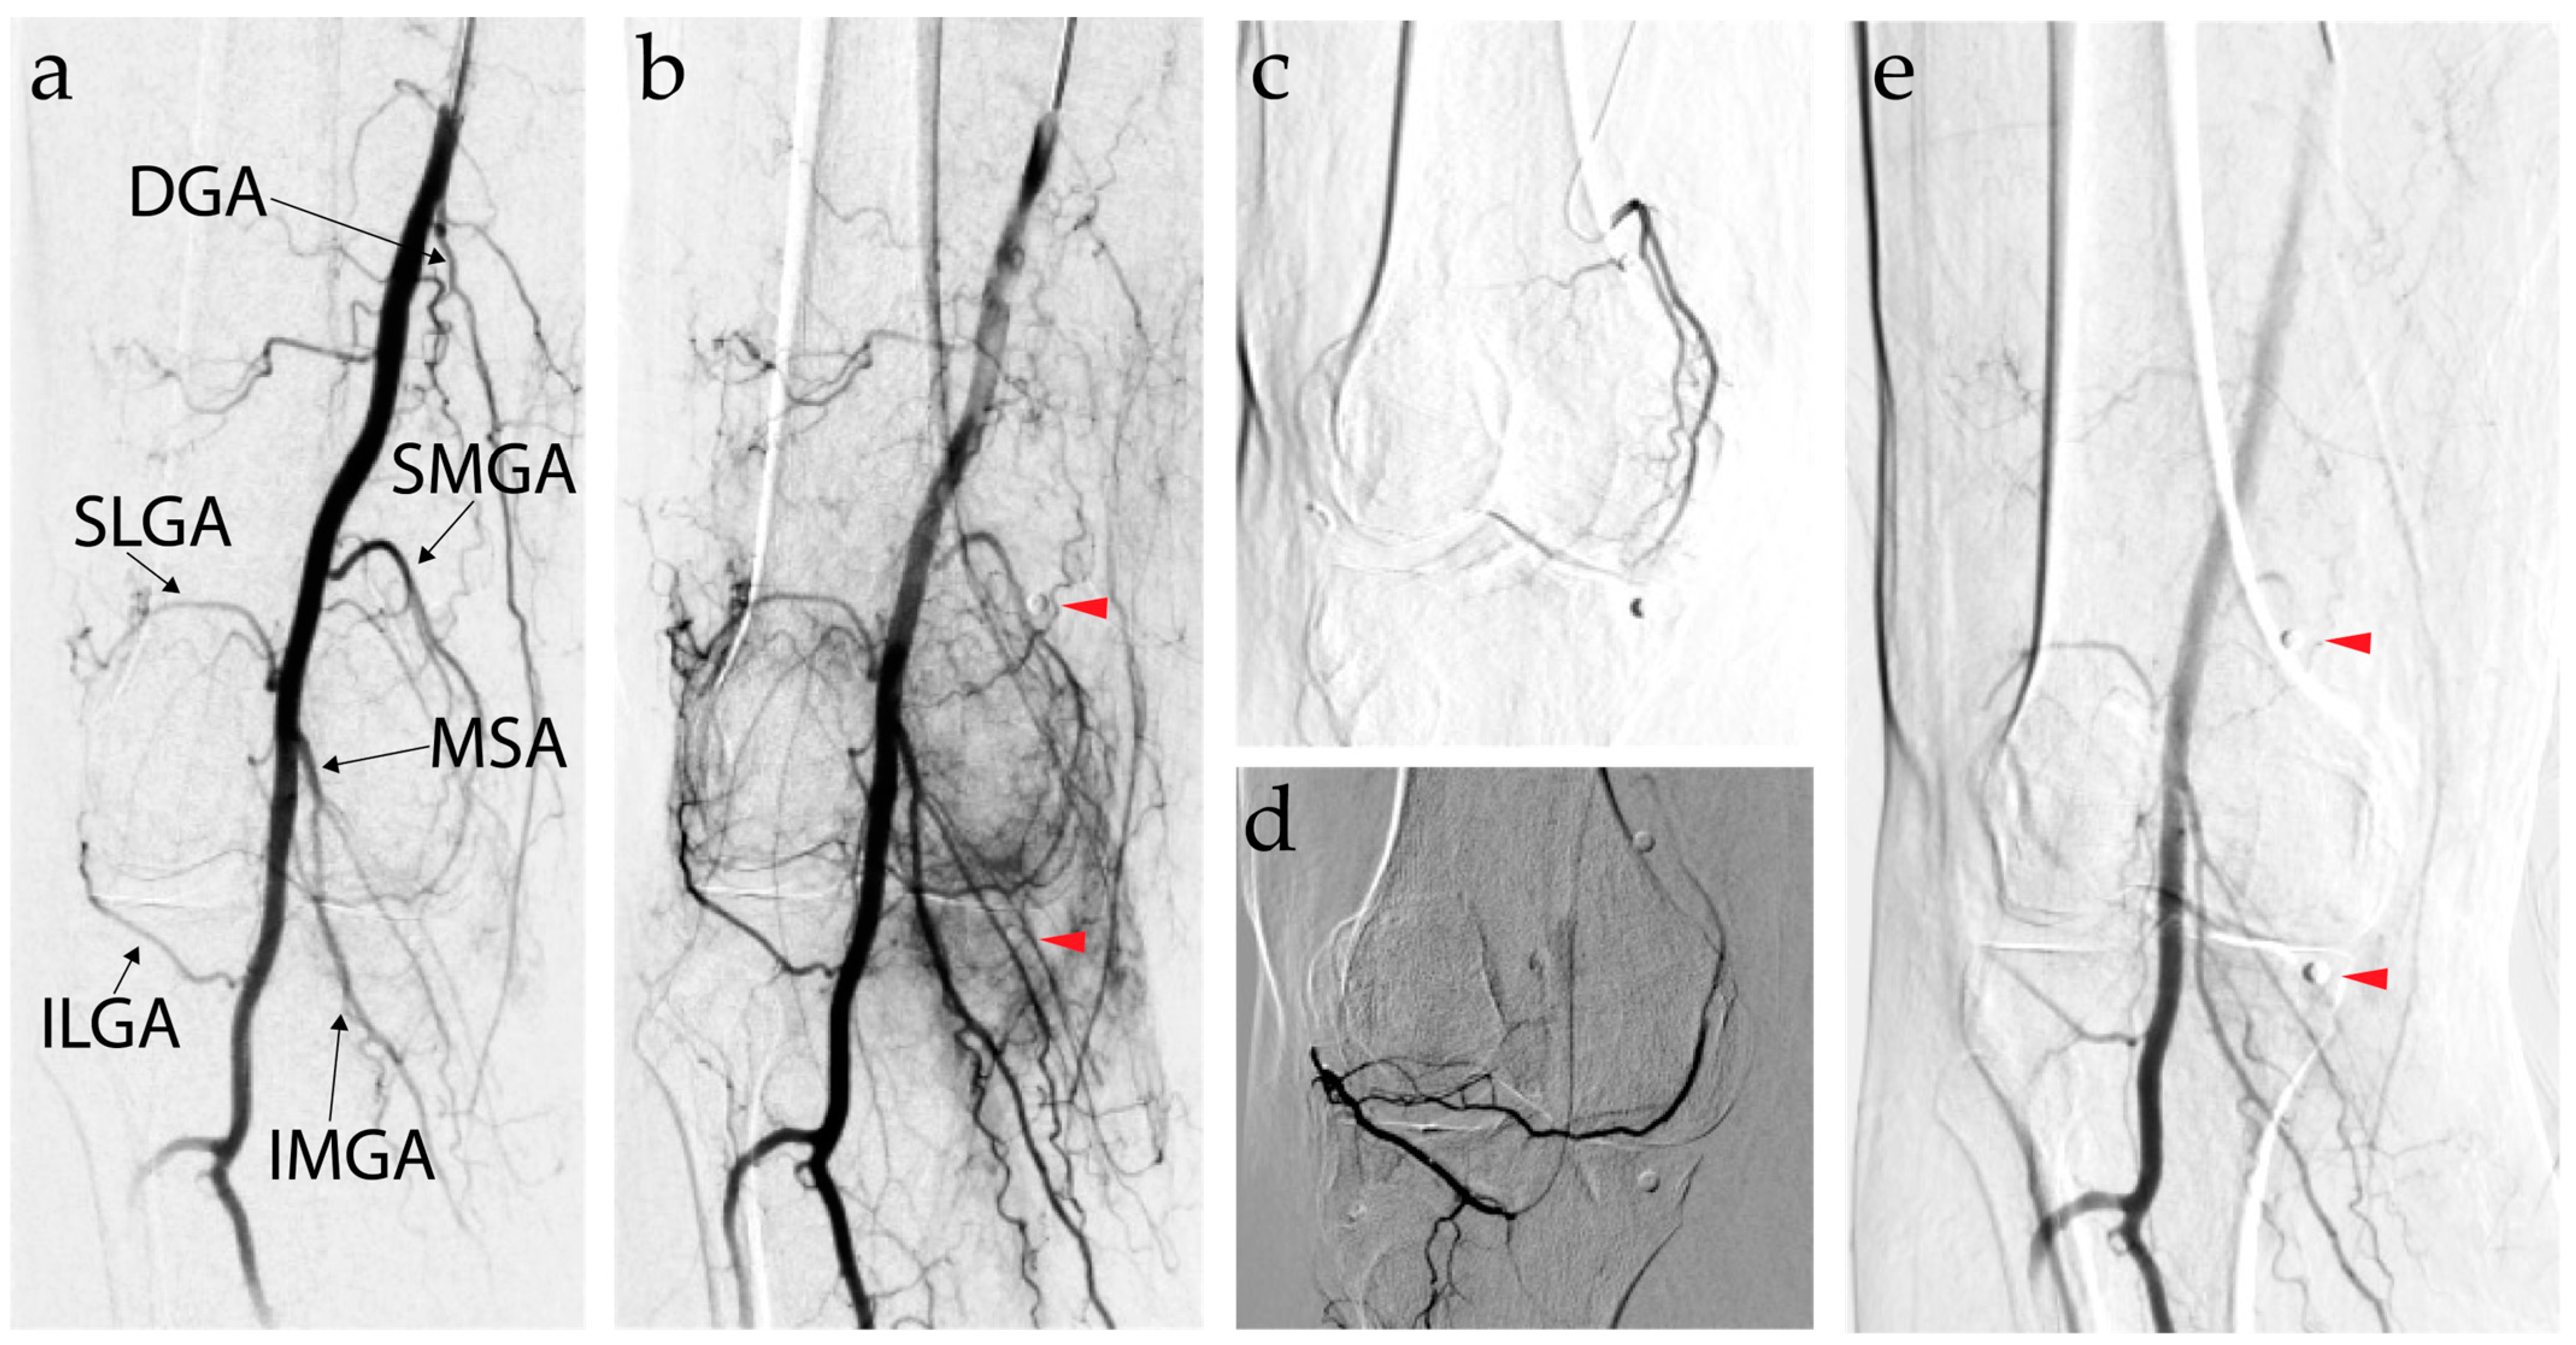

7.3. Genicular Artery Embolization Technique

7.1. Background and Mechanism of Action of Genicular Artery Embolization

7.2. Efficacy of Genicular Artery Embolization